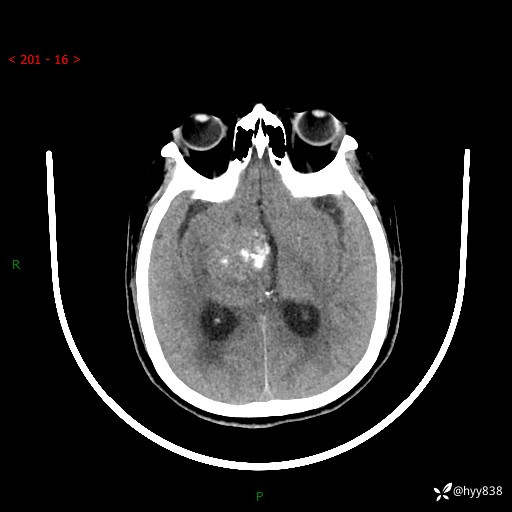

颅脑CT平扫